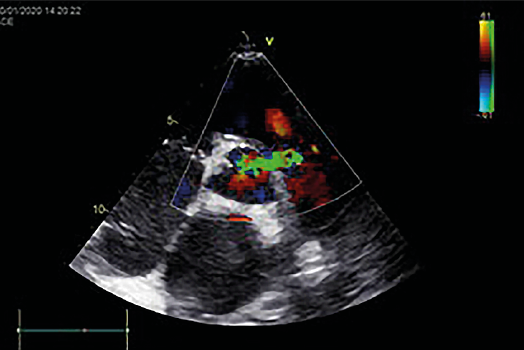

ECG: right EHA deviation, sinus tachycardia with HR 120 bpm, ST segment on the isoline. Echo: LV EF 54 %, vegetation on the aortic cusp 1.2 x 2.0 cm (Fig. 2), severe aortic insufficiency, an open abscess of the aortic root with a fistula between the aortic root and the right ventricular outflow track (Fig. 3), an open abscess of the MV anterior cusp with a developed perforation, severe insufficiency of the MV (Fig. 4). Dilation of left and right atria, moderate tricuspid valve insufficiency, stage 2 pulmonary hypertension, fluid in both pleural cavities.

Fig. 2. Vegetations on the AV cusps